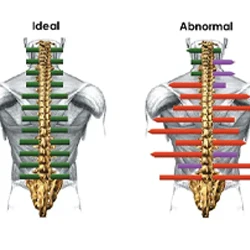

Surface Electromyography

Surface Electromyography (sEMG) is a non-invasive, computer-based technique that records the electrical impulses of the nerve at rest. It allows us to evaluate muscle tension around the spine, showing muscular compensation patterns for various spinal disorders.